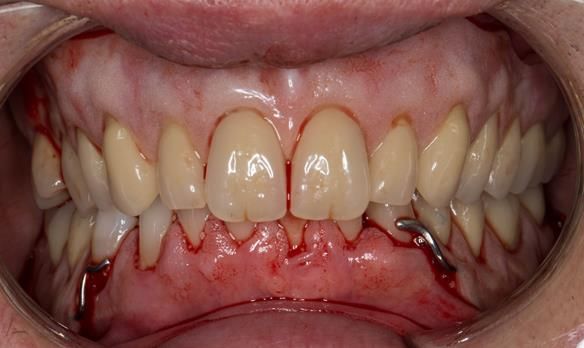

This 52 year old man was referred to me from his general dental practitioner in 2018.

10 years prior to consultation the patient's general dentist diagnosed periodontitis and referred him to Manchester Dental Hospital. He received a treatment plan to manage the periodontitis. Unfortunately, this was not acted on. Four years ago gaps developed between the upper front teeth. Orthodontic treatment was provided to align the teeth. A bonded retainer was fitted onto the upper front teeth. Approximately one year prior to consultation with me the patient noticed the teeth moving again. He consulted his orthodontist, who advised no further orthodontic treatment. One month prior to the consultation with me the upper left central incisor fell out whilst eating.

- Generalised periodontitis; stage IV grade C: currently unstable, risk factors: smoker.

- The remaining maxillary teeth had hopeless prognosis in the short term. They exhibited 80 - 100% alveolar bone loss with increased mobility (Grade 2 - 3).

- The lower right second premolar and lower left first premolar (LR5 LL4) had hopeless prognosis in the short term. They exhibited 80 - 100% alveolar bone loss with grade 3 mobility.

- The remaining mandibular teeth had approximately 30 - 50% alveolar bone loss with grade 1 mobility.

The clinical situation and treatment process is shown in detail below with photographs.